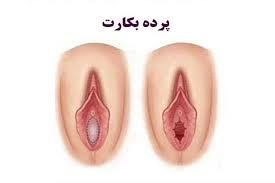

پردهی بکارت یک بافت گوشتی نازک است که در ابتدای ورودی واژن زن قرار دارد. این ورودی شکلهای مختلفی دارد و در بیش از نیمی از خانمها بعد از برقراری رابطهی جنسی و یا ورود یک جسم خارجی به داخل واژن پاره میشود و با یا بدون خونریزی این پارگی را نشان میدهد. از آن جایی که مسئلهی باکرگی در فرهنگها و مذهبهای مختلف تعاریف متنوعی دارد و از نقطهنظرهای مختلفی به این مسئله نگاه میشود، برخی از افرادی که علارغم باورها و اعتقادات مذهبی و عرفیشان، رابطهی جنسی داشتهاند و دچار پارگی پردهی بکارت شدهاند، با مشکل مواجه شدهاند و به ترمیم پردهی بکارت فکر میکنند.

هایمنوپلاستی (hymenoplasty) یا عمل جراحی ترمیم بکارت، عملی است که طی آن کسی که قبلا به هر دلیلی باکرگی خود را از دست دادهاست، میتواند با بازسازی پردهی بکارت، مجددا باکره به نظر بیاید. در این جراحی معمولا پردهی بکارت به شکلی بازسازی میشود که بعد از برقراری رابطه جنسی، قابلیت خونریزی داشتهباشد و باکرگی خانم را به این شکل نشان دهد. توجه داشتهباشید که در هایمنوپلاستی از پردهی بکارت مصنوعی استفاده نمیشود و خود بافت به شکلی جراحی میشود که دستنخورده جلوه کند.

وقتی پرده بکارت پاره میشود، ممکن است بقایایی از آن باقی بماند یا نه. در ادامه در دو قسمت انواع روشهای جراحی برای هر دو مورد را بررسی میکنیم:

پرده بکارت یک غشای ظریف است که در دهانه واژن دختران قرار دارد و از عفونت جلوگیری می کند.